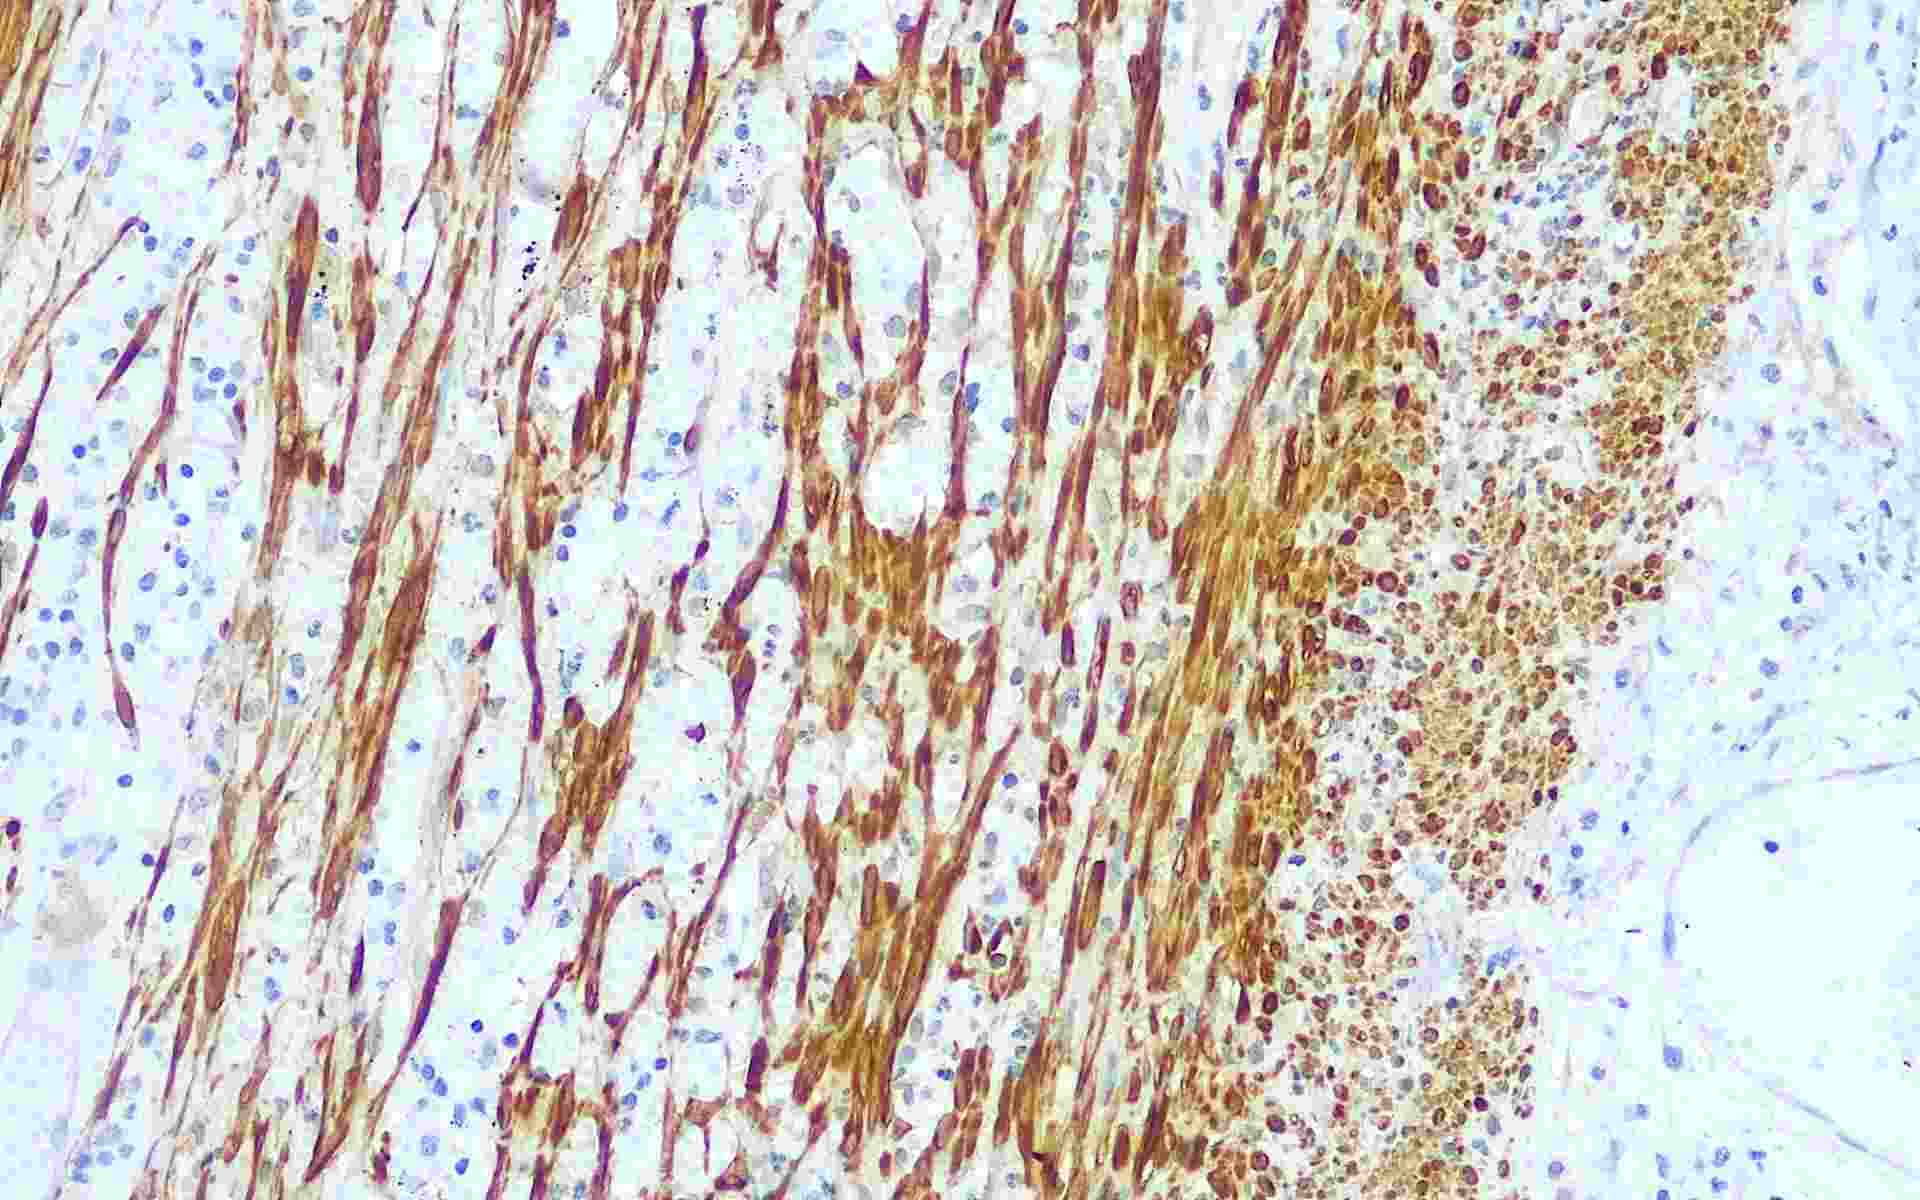

Calponin-1是一种结合肌动蛋白,原肌球蛋白钙调蛋白,分子量为34kDa,是平滑肌细胞的一种特异性蛋白,具有调节平滑肌收缩的功能。Calponin-1标记平滑肌组织以及乳腺病变时的肌上皮细胞,可用于平滑肌肿瘤和乳腺病变中肌上皮细胞分布的研究。

• CALP阑尾